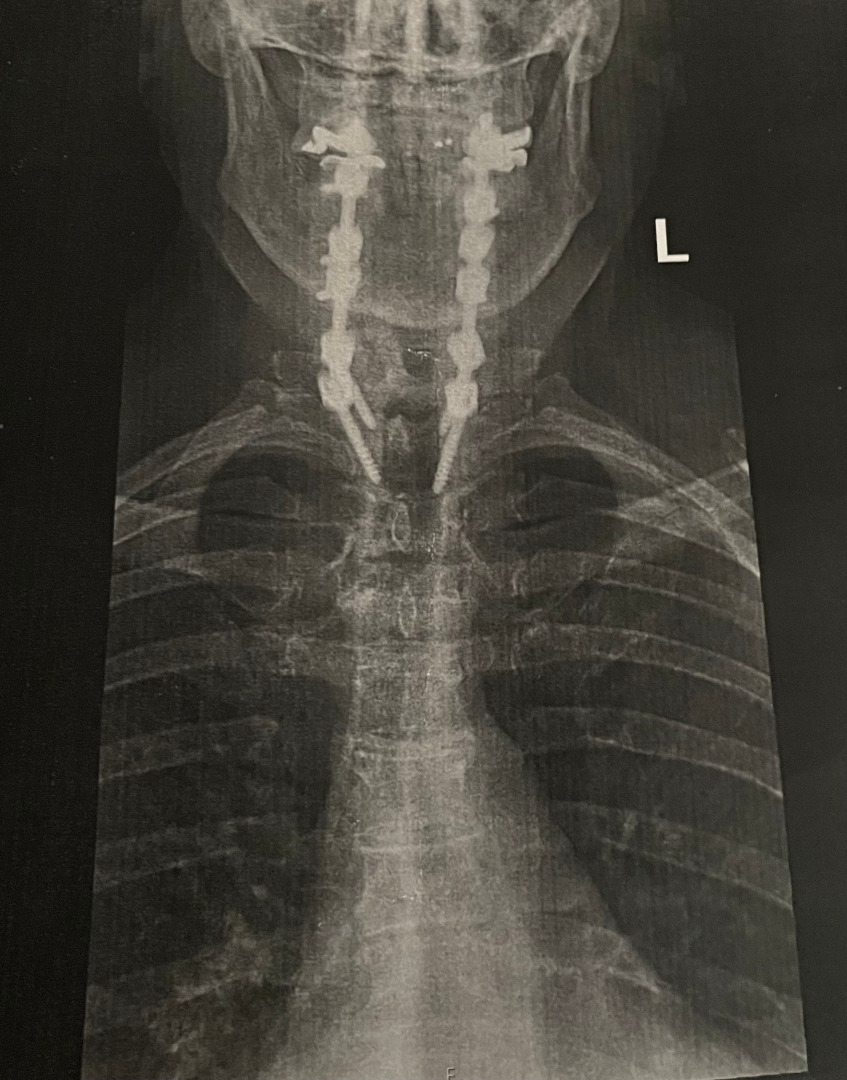

When I was faced with having a very radical spine surgery, I thought my theatre days, as I knew them, were over. In December 2023 I had a six level (C2 to T2) spinal fusion. My spine was crumbling from degenerative disc disease, and spinal stenosis. My surgeon reinforced my spine with two 12” titanium rods and fourteen screws. I was told I may never walk again; but I’m walking! I have permanent nerve damage in both feet and both hands.